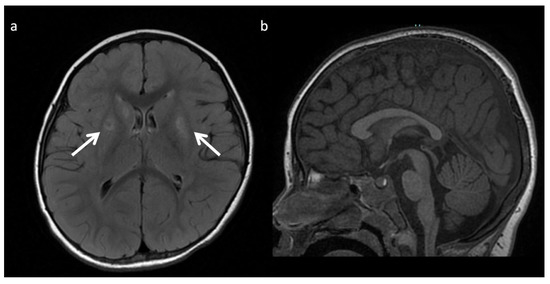

Figure 7.

Metachromatic leukodystrophy in a 16-month-old female who presented with loss of developmental milestones. (a) Axial T2WI and (b) axial DWI demonstrate cerebral volume loss with ex vacuo ventriculomegaly, a widespread leukodystrophy with increased white matter signal sparing the U-fibers (arrows) and involving corpus callosum, and reduced diffusion at leading-edges of active demyelination. (c) SV-MRS over the left periatrial white matter shows elevated Lac, severely depleted NAA, and slightly elevated Cho and mI. Findings are consistent with considerable axonal damage and loss of the white matter.

Lysosomal storage disease: GM2 gangliosidoses, including Tay-Sachs disease and Sandhoff disease (Figure 5), can show characteristic T2 hypointensity in the ventral thalami and T2 hyperintensity in the basal ganglia and dorsal thalami [28]. Krabbe disease (Figure 6) may show diffuse thalamic T2 hypointensity extending to the corticospinal tracts, as well as signal abnormalities in the cerebral and cerebellar white matter, especially the dentate hila and posterior cerebral white matter (centrifugal and posteroanterior gradient often with a tigroid pattern) and variable enlargement of the optic nerve and chiasm due to accumulation of globoid cells; MR phenotypes vary with age [3,8,10,29]. Post-contrast enhancement of multiple cranial nerves and the cauda equina is also characteristic. Metachromatic leukodystrophy (Figure 7) and Krabbe disease may have overlapping imaging features; however Krabbe disease typically spares the callosal genu and more often involves the internal capsules and brainstem [30]. Neuronal ceroid lipofuscinosis may also demonstrate thalamic T2 hypointensity, with cortical atrophy as another prominent feature [9].